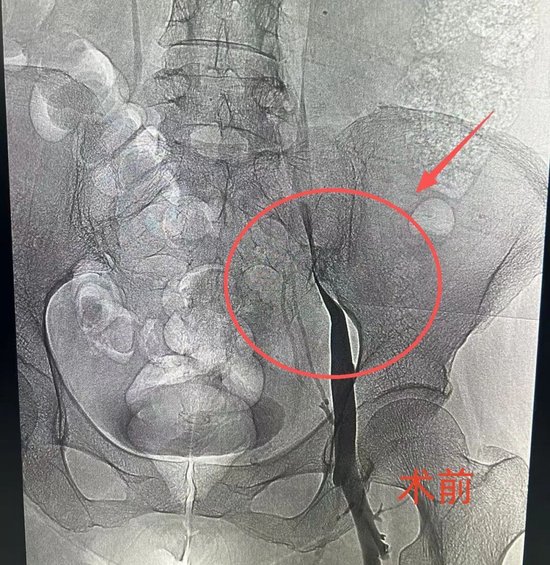

在局部麻醉下,介入科团队经右侧腘静脉成功穿刺,造影显示右髂外静脉存在约95%的极重度狭窄。团队随即对狭窄处施行了球囊扩张及支架植入术,术后造影显示支架定位精准,血流通畅,患者术前的酸胀感随之消失,手术顺利完成。